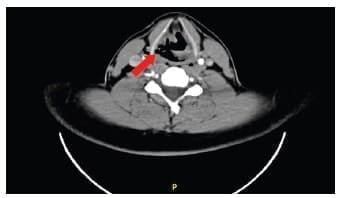

En un paciente se observó lesión de vía aérea en TC, confirmada mediante fibrobroncoscopia, la cual consistía en una lesión laríngea a nivel del hioides (Figura 2), como consecuencia de una colisión en motocicleta con trauma cervical directo, que fue manejada de manera conservadora.

Figura 2. Tomografía computarizada de cuello con evidencia de disrupción de la pared laríngea a nivel del hioides (flecha roja), con presencia de aire extraluminal, el cual se diseca hasta el espacio mediastinal. Fuente: parte de la historia clínica del paciente.